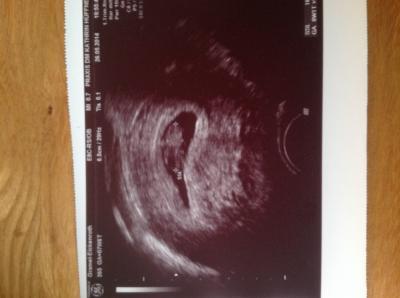

1.FA Termin heut gehabt. Alles bestens. Herzchen blubbert kräftig . Der stolze Papa hat sich in das Ubild total verliebt. Hat es sich jetzt in das Portmonee gesteckt. Nächste Woche muss ich zur Blutabnahme, und dann bekomme ich meinen neuen Mutterpass.

Bild zu 1. FA Termin - Forum für Januar - Mamis

ist aber auch echt ein schönes Bild! Wie weit bist du? Es sieht alles schon so groß aus!

War gestern 7+6 laut RuB Rechner. Der Frauenarzt hat gestern 8+1 gemeint. Also irgendwo in der 9 Woche.

Wie schön. Man sieht schon soviel